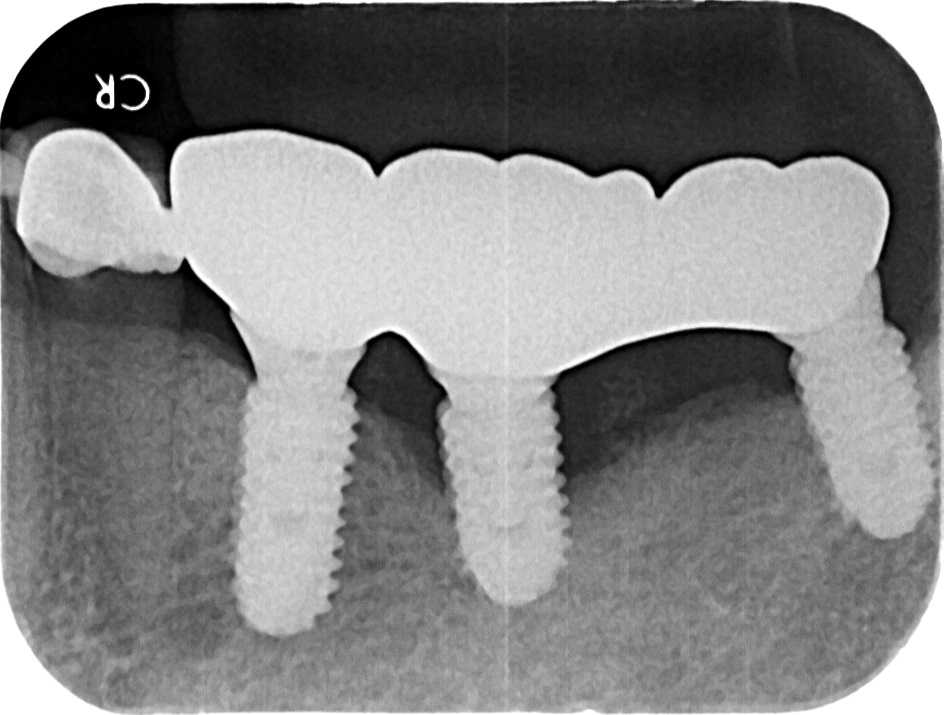

All on 4 / All on X